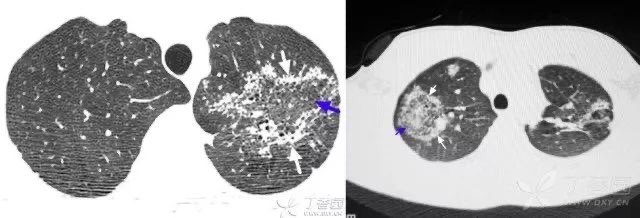

患者脑出血入院,治疗后呼吸深大急促,并出现上肢与脸部水肿。

急查胸部 CT,见双肺自肺门向外弥漫基本对称的片絮状影(蓝箭),双侧胸腔后部可见液体(白箭)。

顾名思义,表现与晕征相反,是一种外带密度略高(白箭)于内部磨玻璃密度区(蓝箭)的 CT 表现。一般常见于肺结核和真菌肺炎。